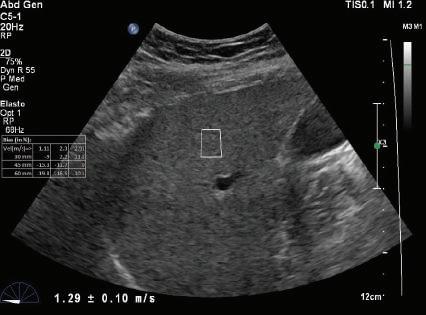

FIG. 1.24 Shear Wave Elastograms of (A) Normal and (B) Cirrhotic Liver. Shear wave velocities measured in liver tissue samples by shear wave elastography indicates a velocity of 1.29 ± 0.10 m/sec in the normal liver compared to a velocity of 4.41 ± 0.17 m/sec in the cirrhotic liver. Increased shear wave velocity is associated with increased tissue stiffness due to hepatic fibrosis. (Courtesy of P. O’Kane, Thomas Jefferson University.)

A - Normal liver

v = 1.29 ± -.10 m/s

B - Cirrhotic liver

v = 4.41 ± -.17 m/s